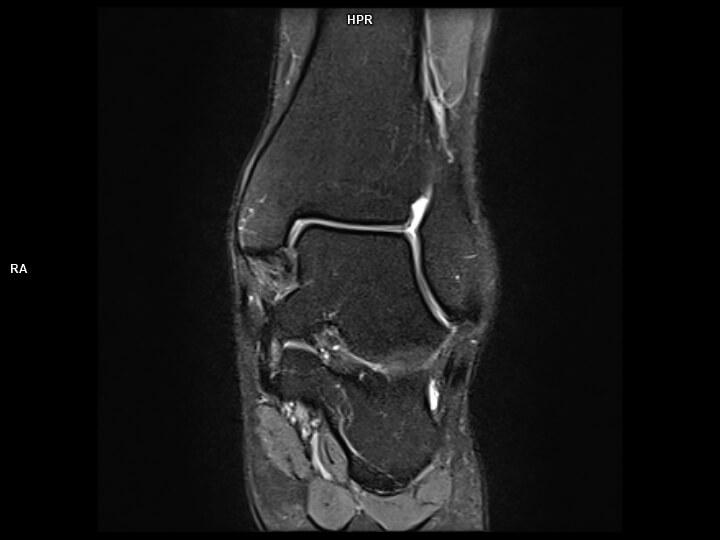

PD FS Cor-MAGNETOM Sola

PD FS Cor-MAGNETOM Sola/Coil-FootAnkle16/Resolution-320/Scan Time-1:34/Aceleration-p2 s2